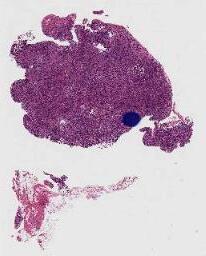

临床资料: 患者,男性,32岁,反复咽部异物感10余天。入住我院耳鼻喉科.专科检查:咽部充血,右侧扁桃体II度肿大,表面溃烂,伴白色分泌物附着,不易拭去。左侧扁桃体正常。血常规:淋巴细胞计数3.95x10^9/L个,淋巴细胞比值59.5%,单核细胞比值12.2%,异型淋巴细胞比值4%,异型淋巴细胞计数0.19x10^9/L个。血EB病毒核酸检测:455.7IU/ml。PET-CT:1、双侧颈部多发高代谢淋巴结,考虑淋巴瘤,累及鼻咽顶后壁、双侧扁桃体,Deauville综合评分为5分,Lugano分期为11期(侵及横隔一侧≥2个淋巴结区域)。2、双侧锁骨区、双侧腋窝、肝门区、双侧腹股沟多发淋巴结,代谢稍高,建议密切随访。

大体所见: 右扁桃体活检